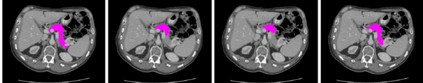

Transformer, the latest technological advance of deep learning, has gained prevalence in natural language processing or computer vision. Since medical imaging bear some resemblance to computer vision, it is natural to inquire about the status quo of Transformers in medical imaging and ask the question: can the Transformer models transform medical imaging? In this paper, we attempt to make a response to the inquiry. After a brief introduction of the fundamentals of Transformers, especially in comparison with convolutional neural networks (CNNs), and highlighting key defining properties that characterize the Transformers, we offer a comprehensive review of the state-of-the-art Transformer-based approaches for medical imaging and exhibit current research progresses made in the areas of medical image segmentation, recognition, detection, registration, reconstruction, enhancement, etc. In particular, what distinguishes our review lies in its organization based on the Transformer's key defining properties, which are mostly derived from comparing the Transformer and CNN, and its type of architecture, which specifies the manner in which the Transformer and CNN are combined, all helping the readers to best understand the rationale behind the reviewed approaches. We conclude with discussions of future perspectives.